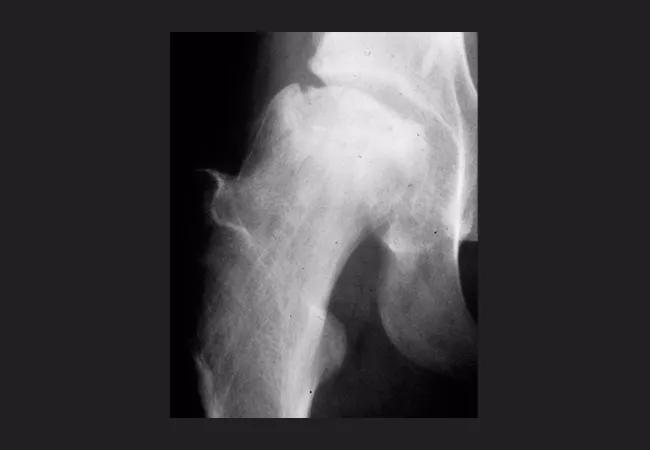

16-ort-2549-mont-inset-figure-02-650pxl-width

MRI of hip osteonecrosis. Arrow indicates a necrotic zone